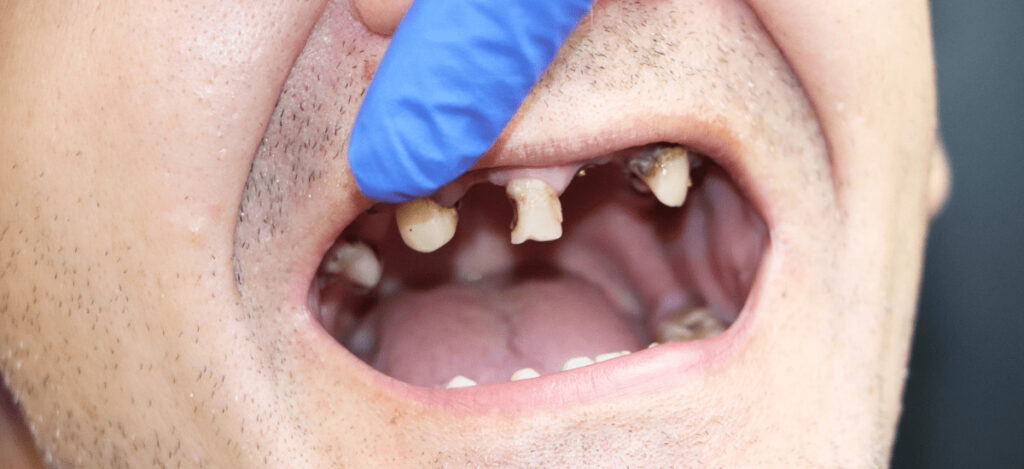

徹底して歯を残す

治療方針

歯というのは、一生ものです。俗に”大人の歯”とも呼ばれる永久歯は、1度失うともう2度と生えてくることはありません。だからこそ、歯をできる限り長く残す”保存”が大切です。歯科における保存治療では、抜歯はなるべく避け、自分の歯を保存しながら機能させることを目的としています。